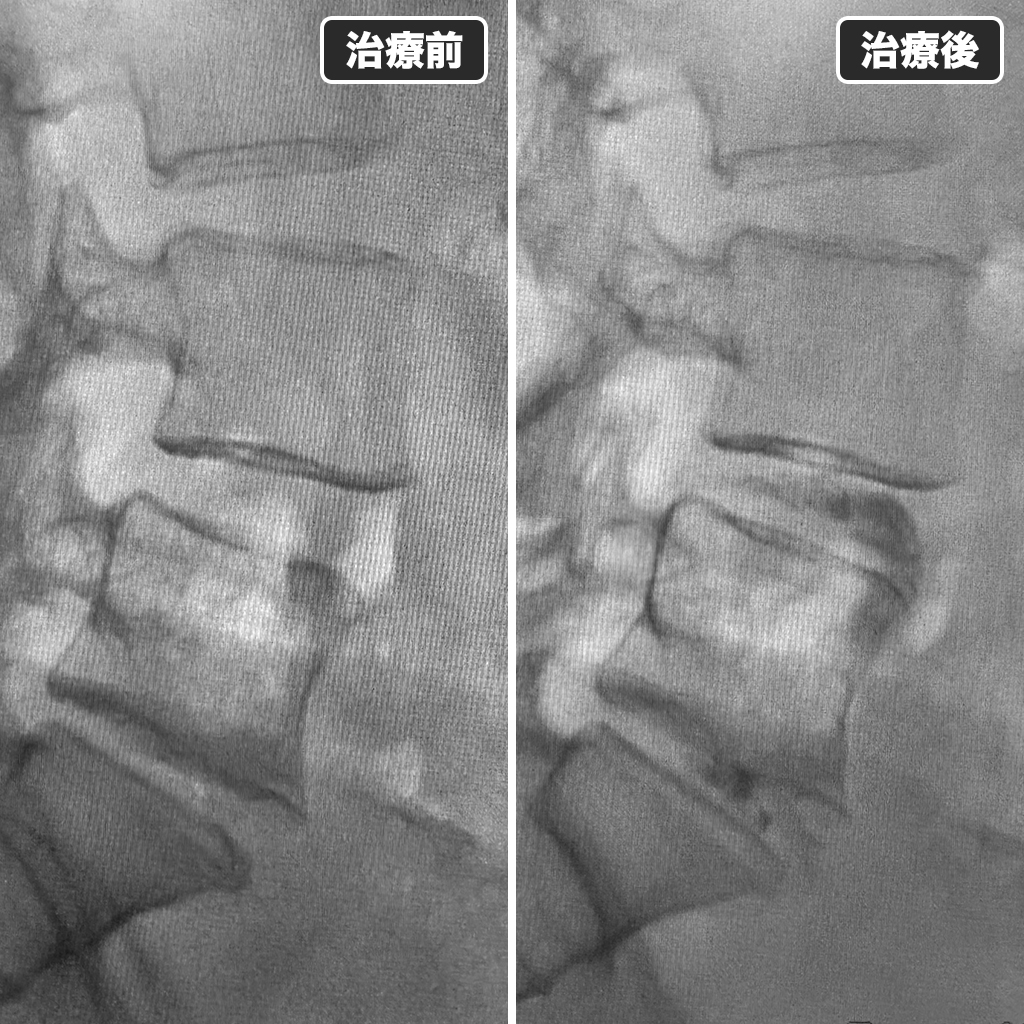

治療前後のレントゲン写真

治療前後のレントゲン写真です、左側が治療前で右側が治療後になります。腰痛発作の改善率は80%以上と期待されます。